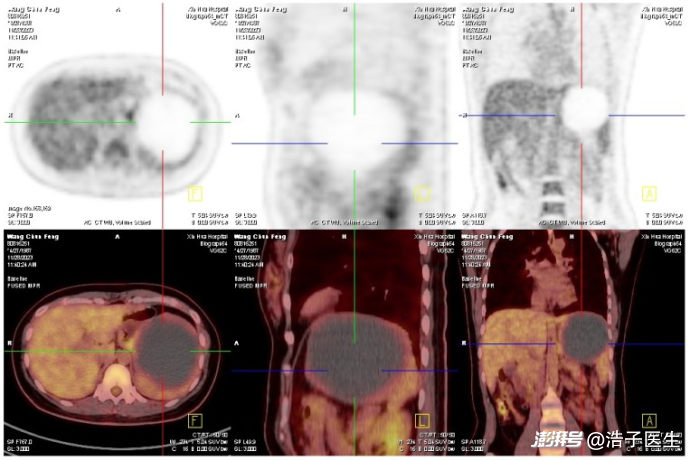

患者PET/CT提示脾脏巨大囊性病灶

一年前,王女士因为突发左上腹疼痛就医,检查发现肿瘤指标CA19-9> 7000 U/ml(正常<25U/ml),当时非常害怕,难道是得了肿瘤?心急如焚的她很快办理了住院,入院后完成腹部增强CT、胃肠镜、PET/CT等检查,然而除了在脾脏上发现一个巨大囊肿外,并没有发现其他明确肿瘤表现。经验丰富的医生团队通过查阅各种资料后发现,脾脏上的这个囊肿可能就是导致CA19-9显著升高的罪魁祸首。通过周密的手术规划,医生团队为其实行了腹腔镜下脾切除术,术后患者恢复良好,病理提示脾脏病灶为表皮样囊肿,一种良性的可发生于全身多部位的囊肿。术后患者定期随访,肿瘤指标也在术后3月完全恢复正常。